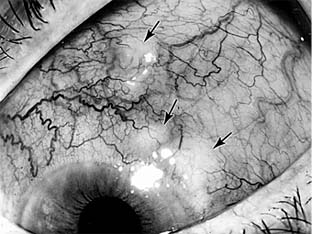

Reiter's disease affects men more frequently than women. The first attack of ocular inflammation usually consists of a self-limited papillary conjunctivitis. It follows, at a highly variable interval, the onset of nonspecific urethritis and the appearance of inflammation in one or more of the weight-bearing joints. Subsequent attacks of ocular inflammation may consist of acute iridocyclitis of one or both eyes, occasionally with hypopyon (Figure 16-4). Rheumatoid arthritis of adult onset may be accompanied by acute scleritis or episcleritis but very rarely by uveitis (Figure 16-5). (See also Chapter 7.)

Figure 16-4

Figure 16-4: Acute iridocyclitis with hypopyon in a patient with Reiter's disease.